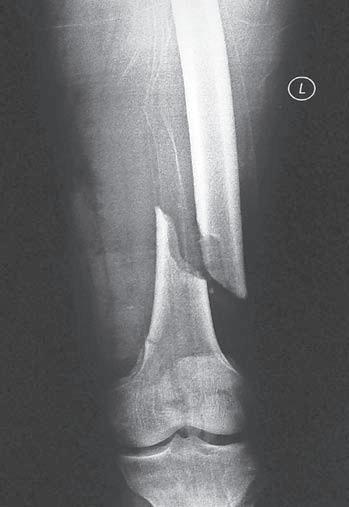

Obr. 2.3 Tříštivá zlomenina diafýzy tibie – hlavní fragmenty, tj. proximální a distální, nejsou v kontaktu. Typ C podle AO klasifikace